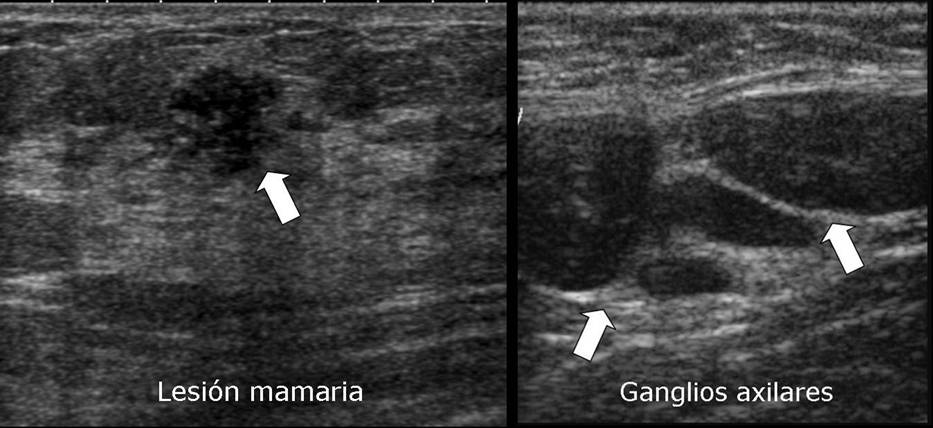

Valoració ecogrà fica dels ganglis axil·lars i nòduls mamaris que s'ajuda d'un contrast ecogrà fic: La zona no contrastada és la zona sospitosa.

En pacients amb diagnòstic de cà ncer de mama i ganglis axil·lars del mateix costat, discretament sospitosos de malignitat per ecografia.

En nòduls mamaris sospitosos per a una millor caracterització i estudi.